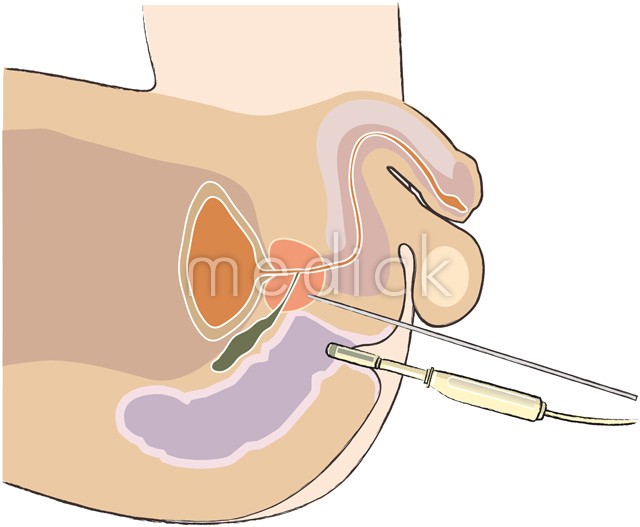

前立腺針生検 経会陰式 のイラスト 医療のイラスト 写真 動画 素材販売サイトのメディック Medick

前立腺針生検 経会陰式 のイラスト 医療のイラスト 写真 動画 素材販売サイトのメディック Medick